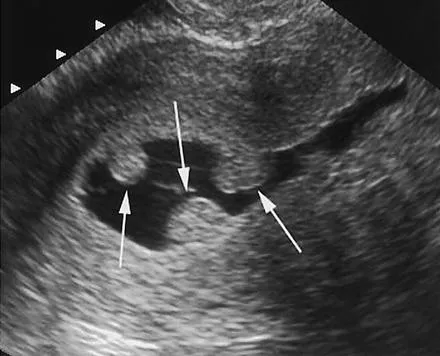

پولیپهای رحمی از جمله تودههای رحم هستند که برای تشخیص آنها روشهای مختلفی وجود دارد. یکی از رایجترین روشها، سونوگرافی ترانس واژینال است که با دقت بالا انجام شده و کل حفره رحم را بررسی میکند. بهترین زمان انجام سونوگرافی جهت تشخیص پولیپ رحم، اواخر سیکل قاعدگی است، اما در زنان یائسه در هر زمان قابل انجام خواهد بود.

اگر نتایج سونوگرافی مشکوک باشد و پولیپ به وضوح دیده نشود، از روشهایی مانند سونوگرافی رنگی رحم، داپلر یا سونوگرافی سهبعدی جهت بررسی دقیقتر استفاده میشود. در برخی موارد، تنها افزایش ضخامت آندومتر مشاهده شده و پولیپ بهطور واضح قابل تشخیص نیست. در این شرایط، انجام هیستروسونوگرافی که در آن رحم با محلول خاصی پر شده و سپس بررسی انجام میشود، به شفافتر شدن نتایج کمک میکند.